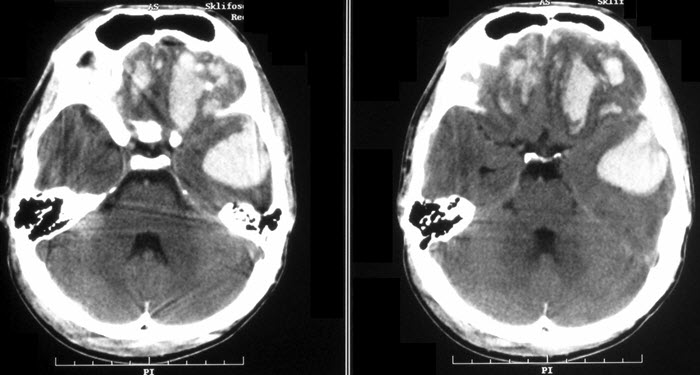

Врачи отмечают, что внутричерепная гипертензия у детей может проявляться различными симптомами, включая головные боли, рвоту, изменения в поведении и ухудшение зрения. Важно, чтобы родители обращали внимание на такие признаки, особенно если они возникают внезапно или сопровождаются другими тревожными симптомами. Диагностика включает нейровизуализацию, такую как МРТ или КТ, что позволяет выявить возможные причины повышения давления внутри черепа.

- Магнитно-резонансная томография является информативным методом при наличии поражений. Она помогает визуализировать структуры головного мозга, обнаруживать аномалии в строении черепа, а также церебральные и сосудистые соединения. Этот метод также используется для подтверждения опухолевых процессов.

Диагностика включает клинический осмотр, сбор анамнеза, а также использование методов визуализации, таких как ультразвуковое исследование, компьютерная томография или магнитно-резонансная томография, чтобы выявить возможные причины повышения давления внутри черепа.